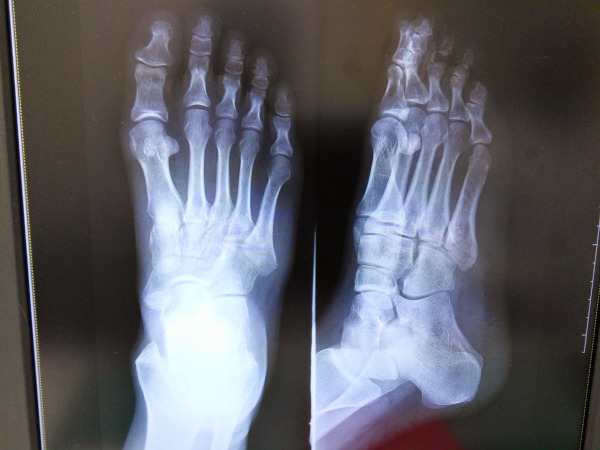

下駄骨折を早く治したいなら絶対に家事はサボった方がいい【自分が骨折した時の記録】

2015年6月1日

日常のつれづれ